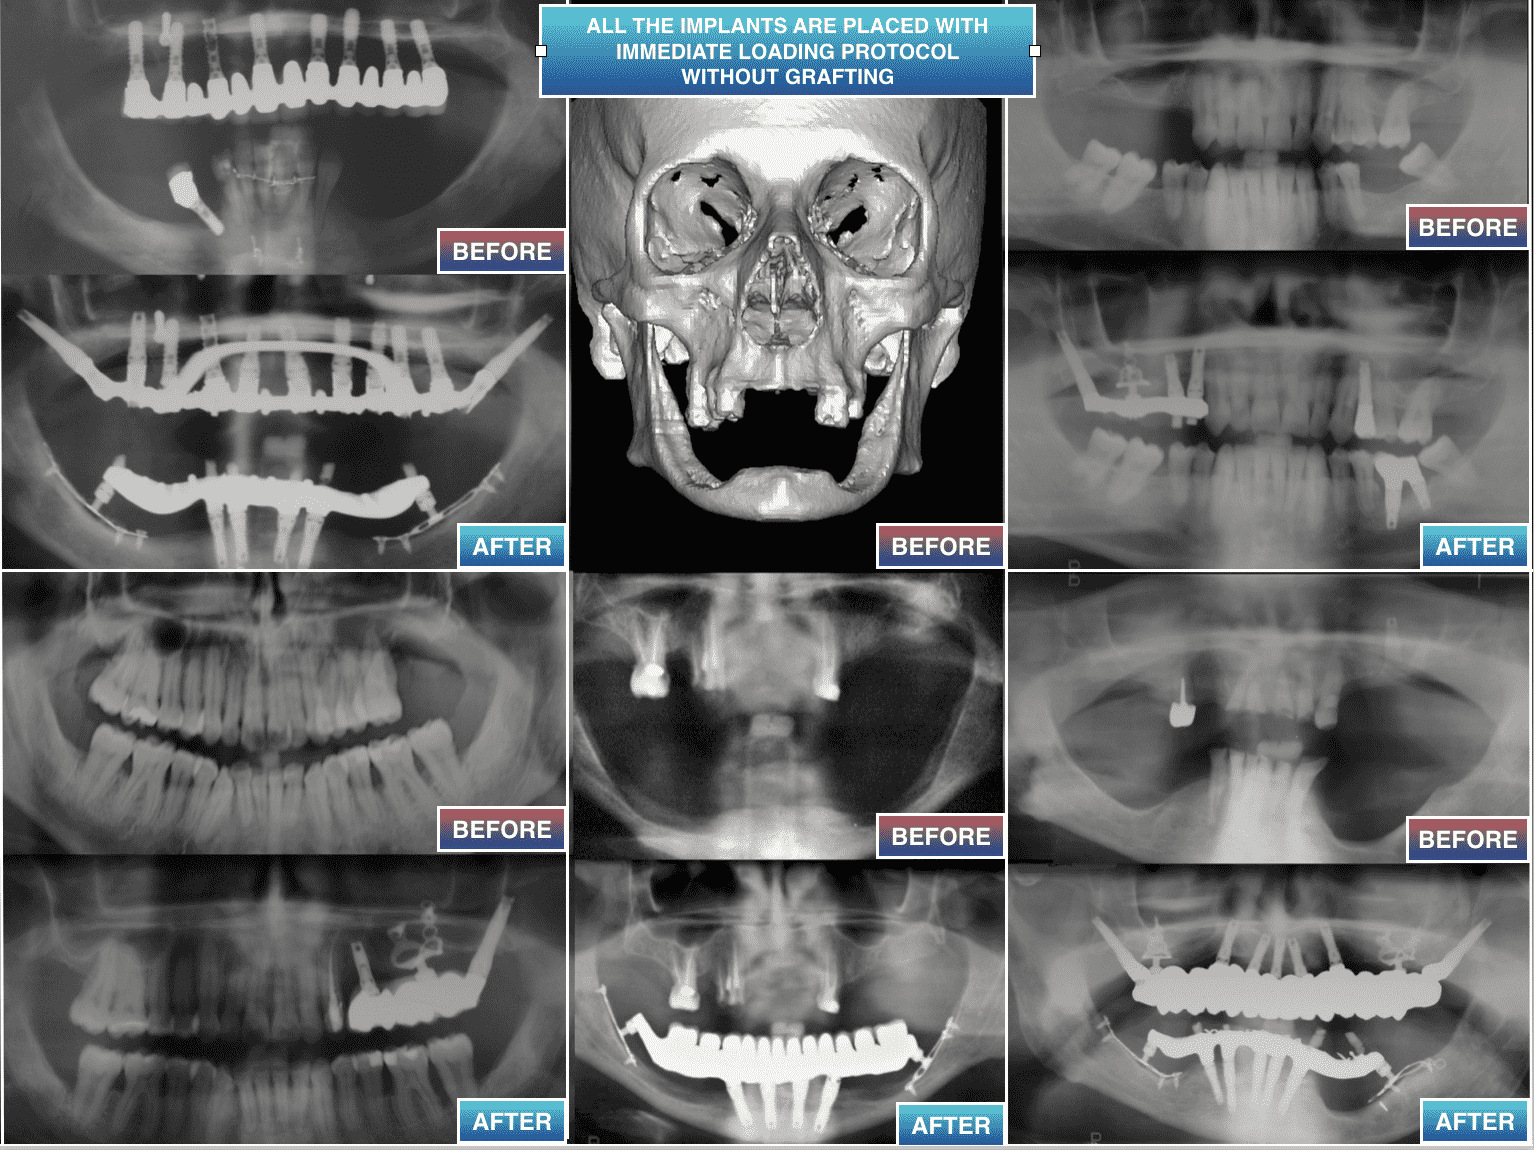

Desde hace más de 30 años hemos practicado procedimientos de cirugía de implantes dentales, enseñados en la Universidad, sin injerto, cuando no pueden aplicarse o cuando han fallado.

- 2)  COMO COLOCAR LOS IMPLANTES SIN INJERTO

SI LA ALTURA DEL HUESO DISPONIBLE ES MENOR DE 4 MM